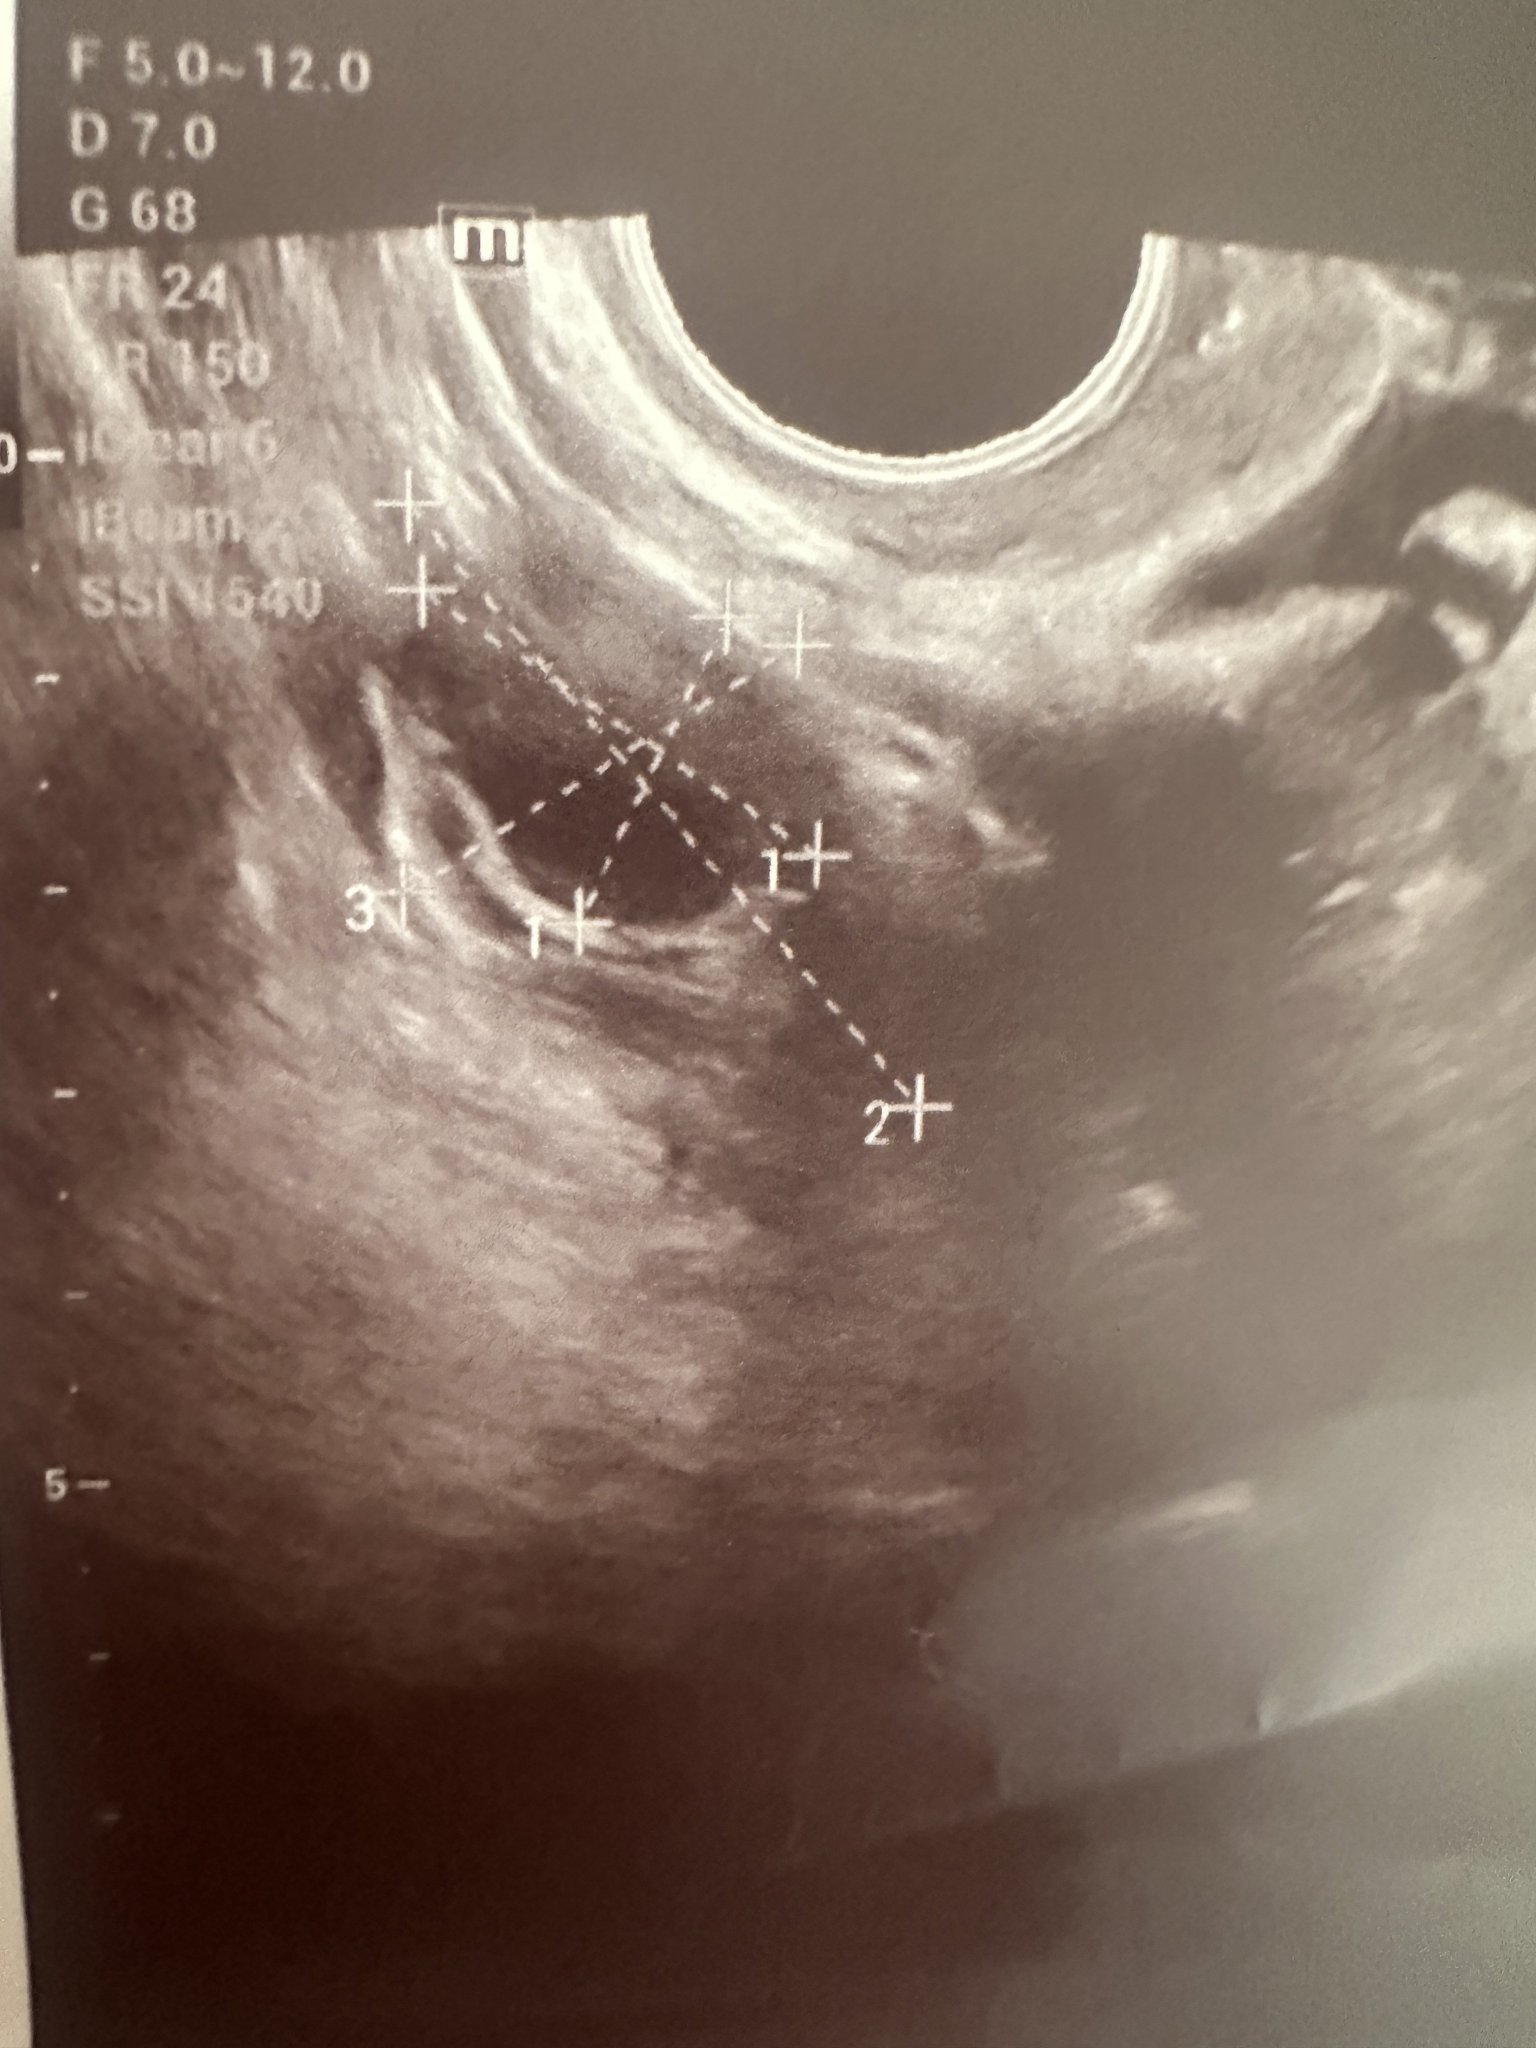

Връщам се от фоликулометрия, но тъй като понякога вярвам повече на вас, околкото на лекари, това защо ми наподобява спукан вече фоликул, а не такъв, който му предстои да се спука?

Скрит текст:

Ако говорим за маркираното - аз малко като самия яйчник го виждам.

Да, и на мен ми прилича на яйчник.